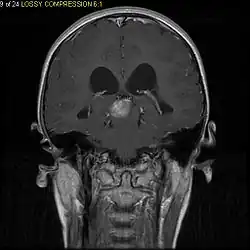

Stereotactic MRI brain scan showing a recurrent postoperative brain stem cystic pilocytic astrocytoma.

Children affected by pilocytic astrocytoma can present with different symptoms that might include failure to thrive (lack of appropriate weight gain/ weight loss), headache, nausea, vomiting, irritability, torticollis (tilt neck or wry neck), difficulty to coordinate movements, and visual complaints (including nystagmus). The complaints may vary depending on the location and size of the neoplasm. The most common symptoms are associated with increased intracranial pressure due to the size of the tumor mass.[2]